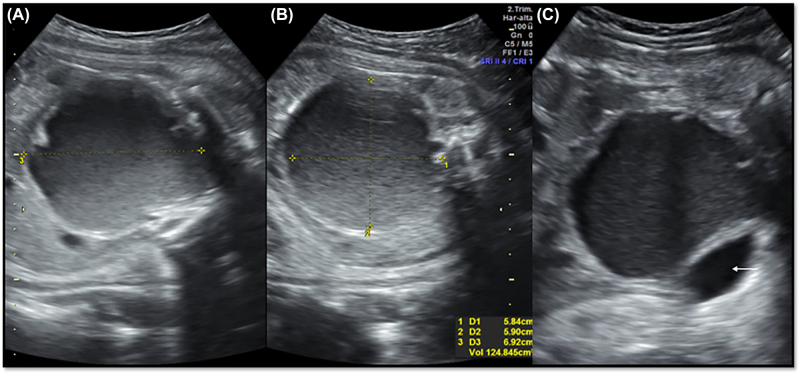

Case presentation: A 19-year-old primigravida presenting at 35 weeks of gestation, with prenatal finding of hydrometrocolpos associated with hypotelorism and microphthalmia. Pre-term cesarean delivery was performed due to breech labor and perinatal death. The autopsy confirmed hydrometrocolpos secondary to vaginal atresia and imperforate hymen, associated with cryptophthalmos, syndactyly, nasal and pinna malformations, confirming the diagnosis of Fraser syndrome.

Conclusions: Fraser syndrome is usually a postnatal diagnosis. The association with genital abnormalities explains the finding of hydrometrocolpos, which could be considered a diagnostic criterion for this syndrome.